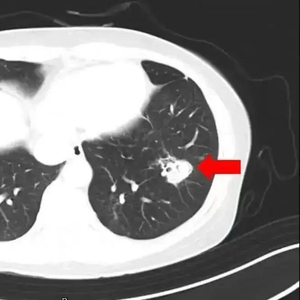

为进一步确诊病情,医生为她进行纤维支气管镜检查及肺泡灌洗液病原体检测,果然发现气道壁上有大量白色菌斑,化验后确认是曲霉菌。